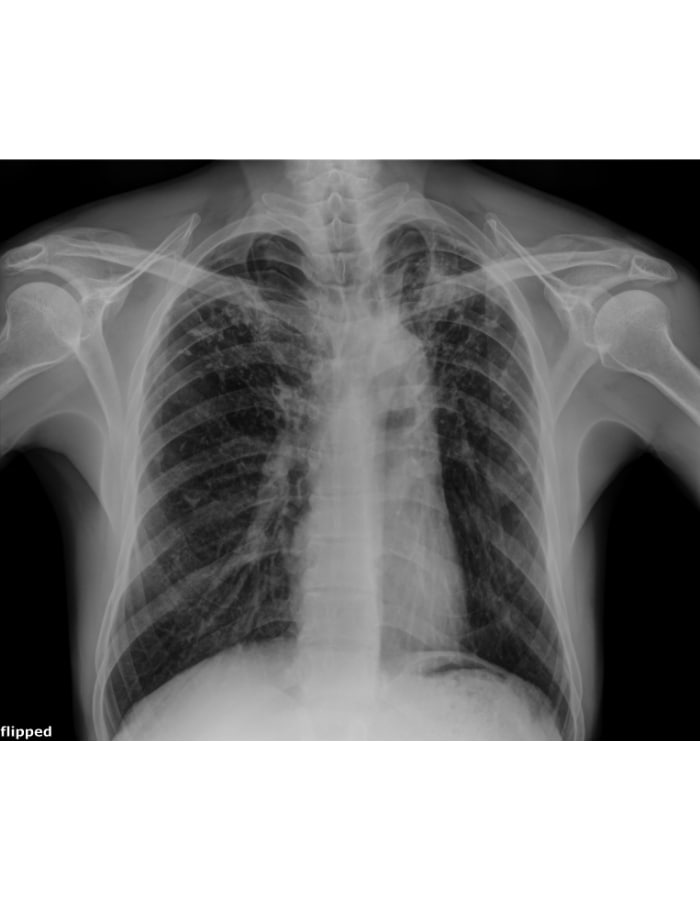

The image above, captured during our routine Active Case Finding in Addis Ababa, is more than just a scan—it is a life saved.

The individual in this image felt perfectly fine and had zero signs or symptoms. However, because of this technology, we found his TB early. He has already started his treatment and is now on the path to a full recovery.